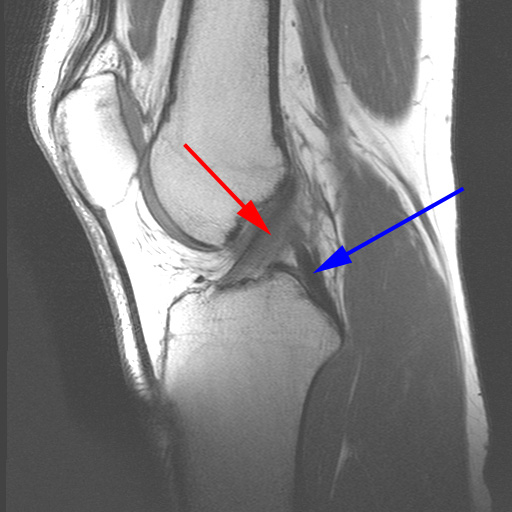

Knæ, Normal (Korsbånd), MR

MR-skanning af knæet der viser normale korsbånd (forreste (rød pil) og bagerste (blå pil)).